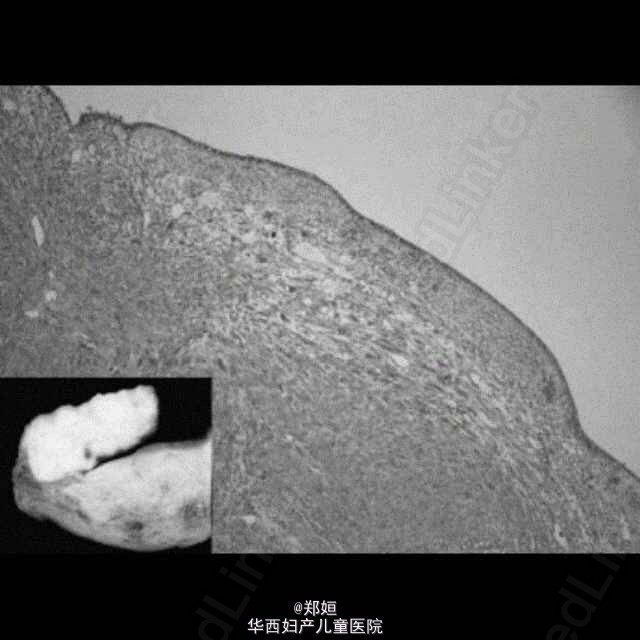

做诊刮,内膜活检提示增生期内膜,可见分散于内膜腺体的不典型子宫内膜基质细胞,部分是多核的,处于上皮层之下。

子宫标本提示有一个息肉样的病灶3.5*2.5*2cm,突向子宫腔,切面灰白色 恢复良好